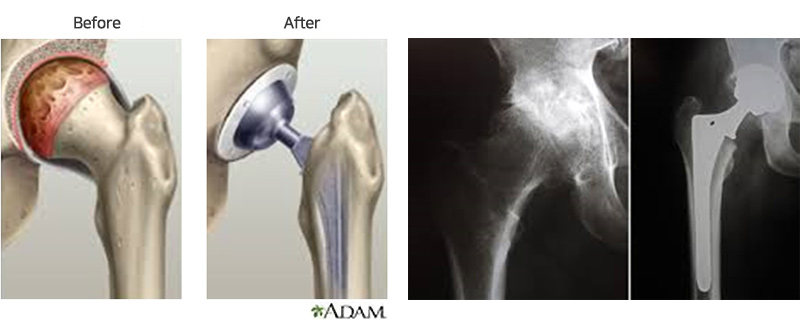

제 5 정형외과전문진료분야 고관절, 슬관절, 족관절, 인공관절 및 관절경, 골다공증

- 대한 정형외과학회 정회원

- 대한 고관절학회 정회원